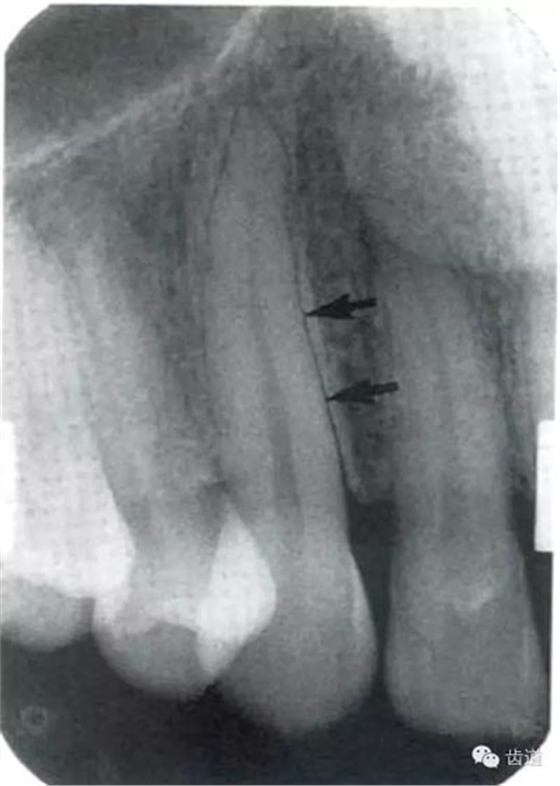

5)下頜管:

位于磨牙牙根尖下方,呈寬約為0.4cm凹面向下邊緣整齊的帶狀密度低的影像,其兩側(cè)有密度高的線條狀影像,為下頜管骨密質(zhì)